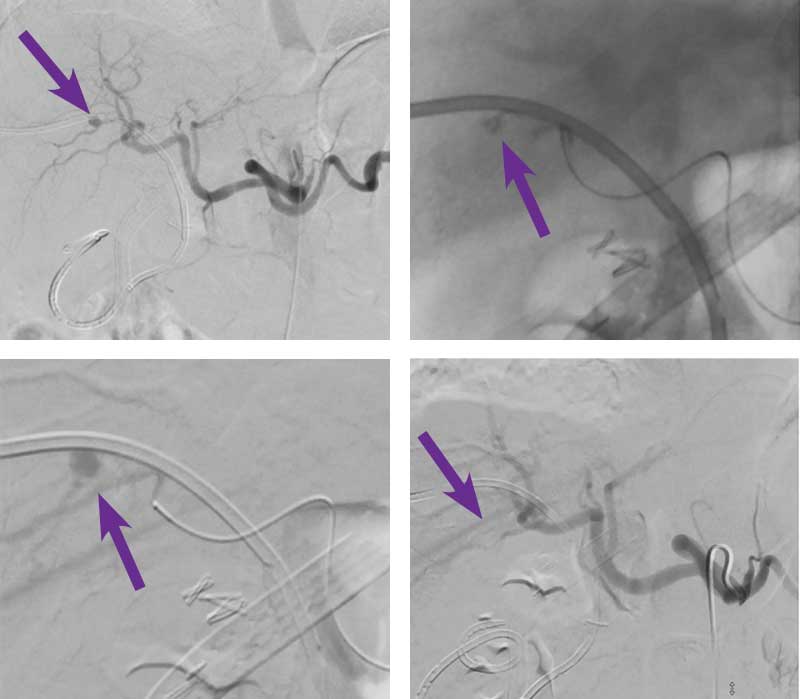

Right hepatic artery pseudoaneurysm embolization

Courtesy of Dr. Abhishek Kumar I Rutgers New Jersey Medical School

Intervention used

Right femoral arterial access was obtained and a 5 F sheath was placed. A 5 F Sos catheter was used to select the celiac artery and an angiogram was performed. Angiography demonstrated a pseudoaneurysm of a right hepatic artery branch adjacent to the biliary drain (arrow). A 2.4 F microcatheter and 0.014” wire were then used to catheterize the vessel supplying the pseudoaneurysm. The vessel was embolized with 0.2 cc of Obsidio Embolic using a slow injection rate to allow the embolic to flow distally into the pseudoaneurysm. Post-imaging depicts the Obsidio Embolic cast. A completion celiac angiogram demonstrated complete embolization of the hepatic artery pseudoaneurysm.

The patient was discharged home 4 hours following the procedure with no recurrence of bleeding.

Scan images from Obsidio right hepatic artery pseudoaneurysm case.